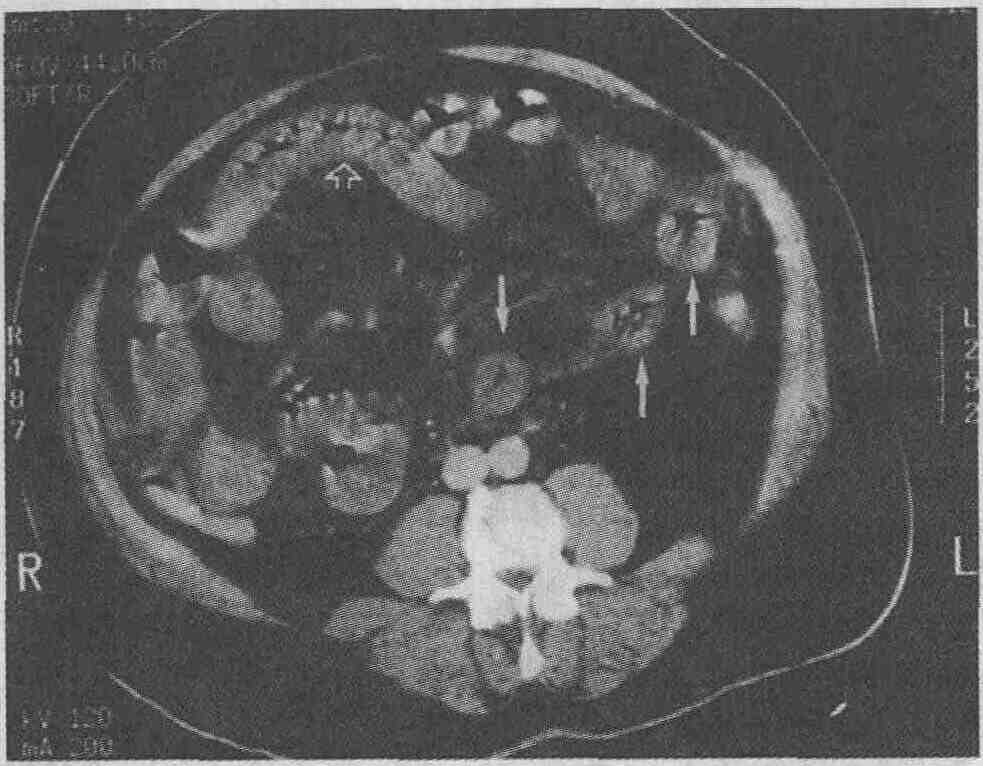

Ультразвуковое сканирование. При ультразвуковом сканировании цирроз характеризуется изменением эхоструктуры печени. Паренхима печени в типичных случаях цирроза выглядит гиперэхогенной с "огрублением" эхосигнала, что делает структуру печени гетероэхогенной. Внутрипеченочные кровеносные сосуды визуализируются плохо. К сожалению, эти изменения неспецифичны: повышение эхогенности паренхимы печени также наблюдается при жировой инфильтрации печени, а гетерогенность эхосигнала — при инфильтрирующих злокачественных опухолях. Более того, не существует прямой корреляции между степенью нарушения функций печени и ультразвуковой картиной. Более специфичными ультразвуковыми признаками цирроза являются наличие узелков на поверхности печени и селективное увеличение хвостатой доли печени (см. рисунок 8А). Если соотношение хвостатой и правой долей печени превышает 96 %, то это позволяет с 96 % точностью диагностировать цирроз. При портальной гипертензии скорость кровотока в неизмененной воротной вене может значительно изменяться, однако при проведении допплеровского исследования выявляется гепатофугальный (ретроградный) кровоток, который считается важным диагностическим признаком. При проведении допплеровского исследования также можно с большей степенью точности выявить наличие коллатеральных кровеносных сосудов, особенно реканализированную параумбиликальную вену. Компьютерная томография. Хотя начальные изменения паренхимы печени на компьютерных томограммах могут быть не видны, этот метод позволяет без особого труда выявлять жировую инфильтрацию, которая является первым признаком алкогольной болезни печени. При этом печень увеличивается в размерах, ее рентгеноконтрастность снижается и становится ниже, чем рентгеноконтрастность селезенки. На поздних стадиях цирроза в типичных случаях размеры печени уменьшаются. Может наблюдаться узловатость контуров печени (связанная с образованием регенераторных узлов, рубцов и зон атрофии), что делает изображение печени гетерогенным. Регенераторные узлы имеют такую же рентгеноплотность, что и паренхима печени, поэтому их можно обнаружить только по деформации контуров печени. Типичными признаками цирроза печени являются увеличение хвостатой доли и латерального сегмента левой доли, а также атрофия правой доли и медиального сегмента левой доли. Жировая ткань брыжейки кишки характеризуется большей рентгеноплотностью, чем забрюшинный и подкожный жир. Кроме того, при проведении компьютерной томографии выявляются варикоз-но расширенные вены, асцит и спленомегалия, связанные с портальной гипертензией (см. рисунок). В отличие от ультразвукового сканирования компьютерная томография не позволяет установить направление кровотока, но дает возможность легко определить протяженность варикозных узлов и наличие коллатеральных сосудов. Магнитно-резонансная томография. Роль МРТ в выявлении цирроза печени невелика, но этот метод позволяет проводить дифференциальную диагностику между циррозом и печеночно-клеточной карциномой. Узлы регенерации обычно характеризуются низкой интенсивностью сигнала при визуализации в режиме Т2 благодаря отложениям гемосидерина, а печеночно-клеточная карцинома — высокой рентгеноплотностью. Гиперпластические аденоматозные узлы без признаков атипии имеют высокую рентгеноплотность при визуализации в режиме Т1 и низкую — при визуализации в режиме Т2, что позволяет провести дифференциальный диагноз с карциномой.

Цирроз печени. А. При ультразвуковом сканировании выявлена уменьшенная в размерах печень, имеющая гиперэхогенную структуру и узловатые контуры, характерные для цирроза. В. При проведении компьютерной томографии выявлены уменьшенная в размерах печень с узловатыми контурами, варикозно расширенные вены (черные стрелки) и сильно выраженный асцит (белая стрелка)